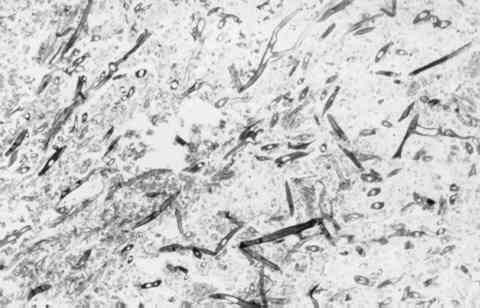

Figura 7

TINCIÓN DE GROCOTT QUE PONE DE MANIFIESTO LA EXISTENCIA DE HIFAS NO TABICADAS Y RAMIFICADAS (MAGNIFICACIÓN ORIGINAL X 100).